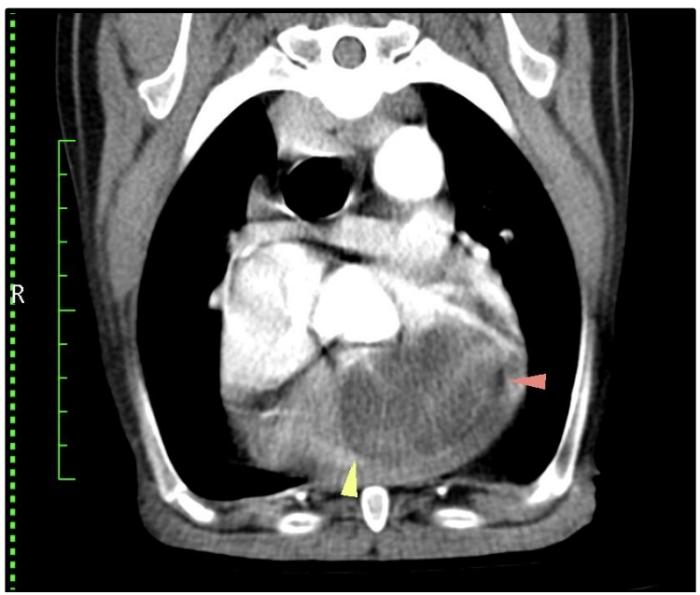

Se propone como diagnósticos diferenciales la presencia de un tumor cardíaco primario vs. metastásico, y se programa una tomografía computarizada (TC) toracoabdominal, para realizar estadio clínico completo, junto con una punción con aguja fina (PAF) de la masa intracardíaca, con el objetivo de obtener un diagnóstico presuntivo (Figura 4). Se añade cimicoxib (2 mg/kg/día) y toceranib fosfato (2.75 mg/kg, lunes-miércoles-viernes) hasta la obtención de los resultados. En la TC se confirma la presencia de neoplasia cardíaca primaria y la citología resulta compatible con un sarcoma, posiblemente un rabdomiosarcoma (RMS).

En base a los resultados obtenidos, se valora la posibilidad de tratamiento con radiofrecuencia (RF), que se descarta por el riesgo de desprendimiento de la masa y taponamiento cardíaco secundario. El tratamiento quirúrgico tampoco está indicado debido al gran tamaño de la masa, su localización y las complicaciones asociadas al procedimiento.